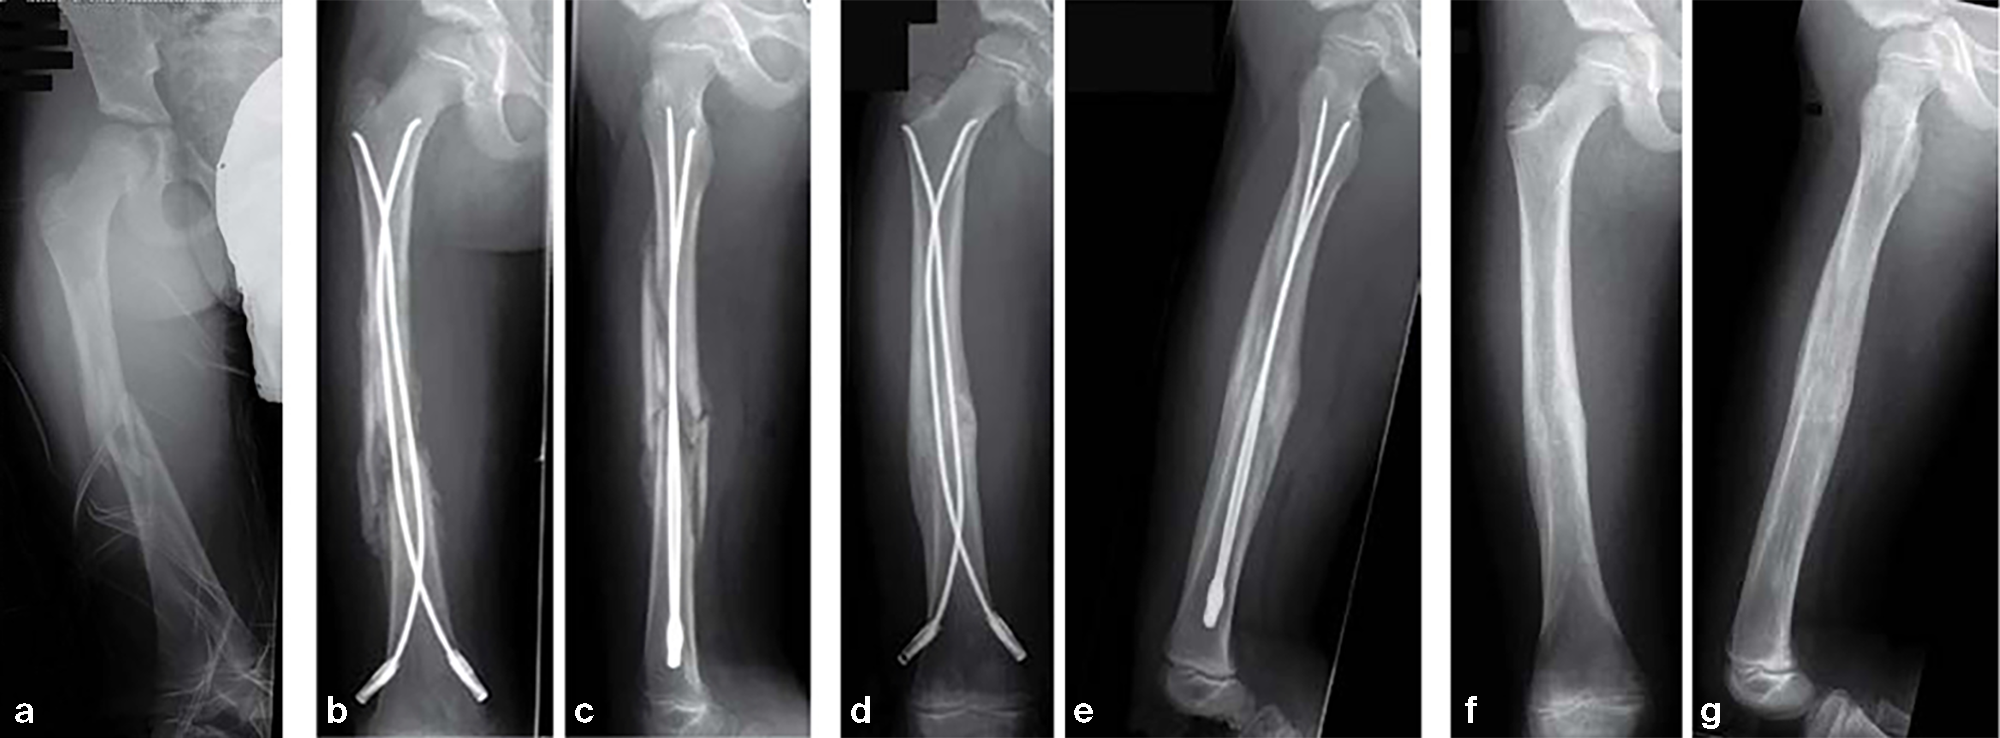

Case of a 8-year old boy with a closed lower leg fracture after football game.

Fig 13a-b: X-rays show a long spiral fracture of the proximal third of the right femur (32D/5.1). Because of the age good indication for ESIN, but some danger of instability is possible.

Fig 13c-d: Postoperative x-rays. A closed reduction and fixation with 3.0 mm TEN was carried out with correct child-oriented alignment. For stability reasons two End Caps became uses. No signs of a shortening can be seen.

Fig 13e-f: AP and lateral view 6 weeks after surgery shows good callus formation and still a perfect alignment.

Full weight bearing was then allowed.

12-year-old boy; snow-board injury long spiral proximal femoral fracture (32D/5.1) primary indication for operation with ESIN and End Cap.

Fig 14a-b: Injury x-rays.

Fig 14c-d: Postoperative x-rays show a correct alignment and length. Fixation with 3.5 mm TEN and End Caps was performed.

Fig 14e: This detail view shows the correct positioning of the End Caps.

Fig 14f-g: 4 1/2 weeks postoperative a good callus and correct alignment was visible, full weight bearing was allowed.